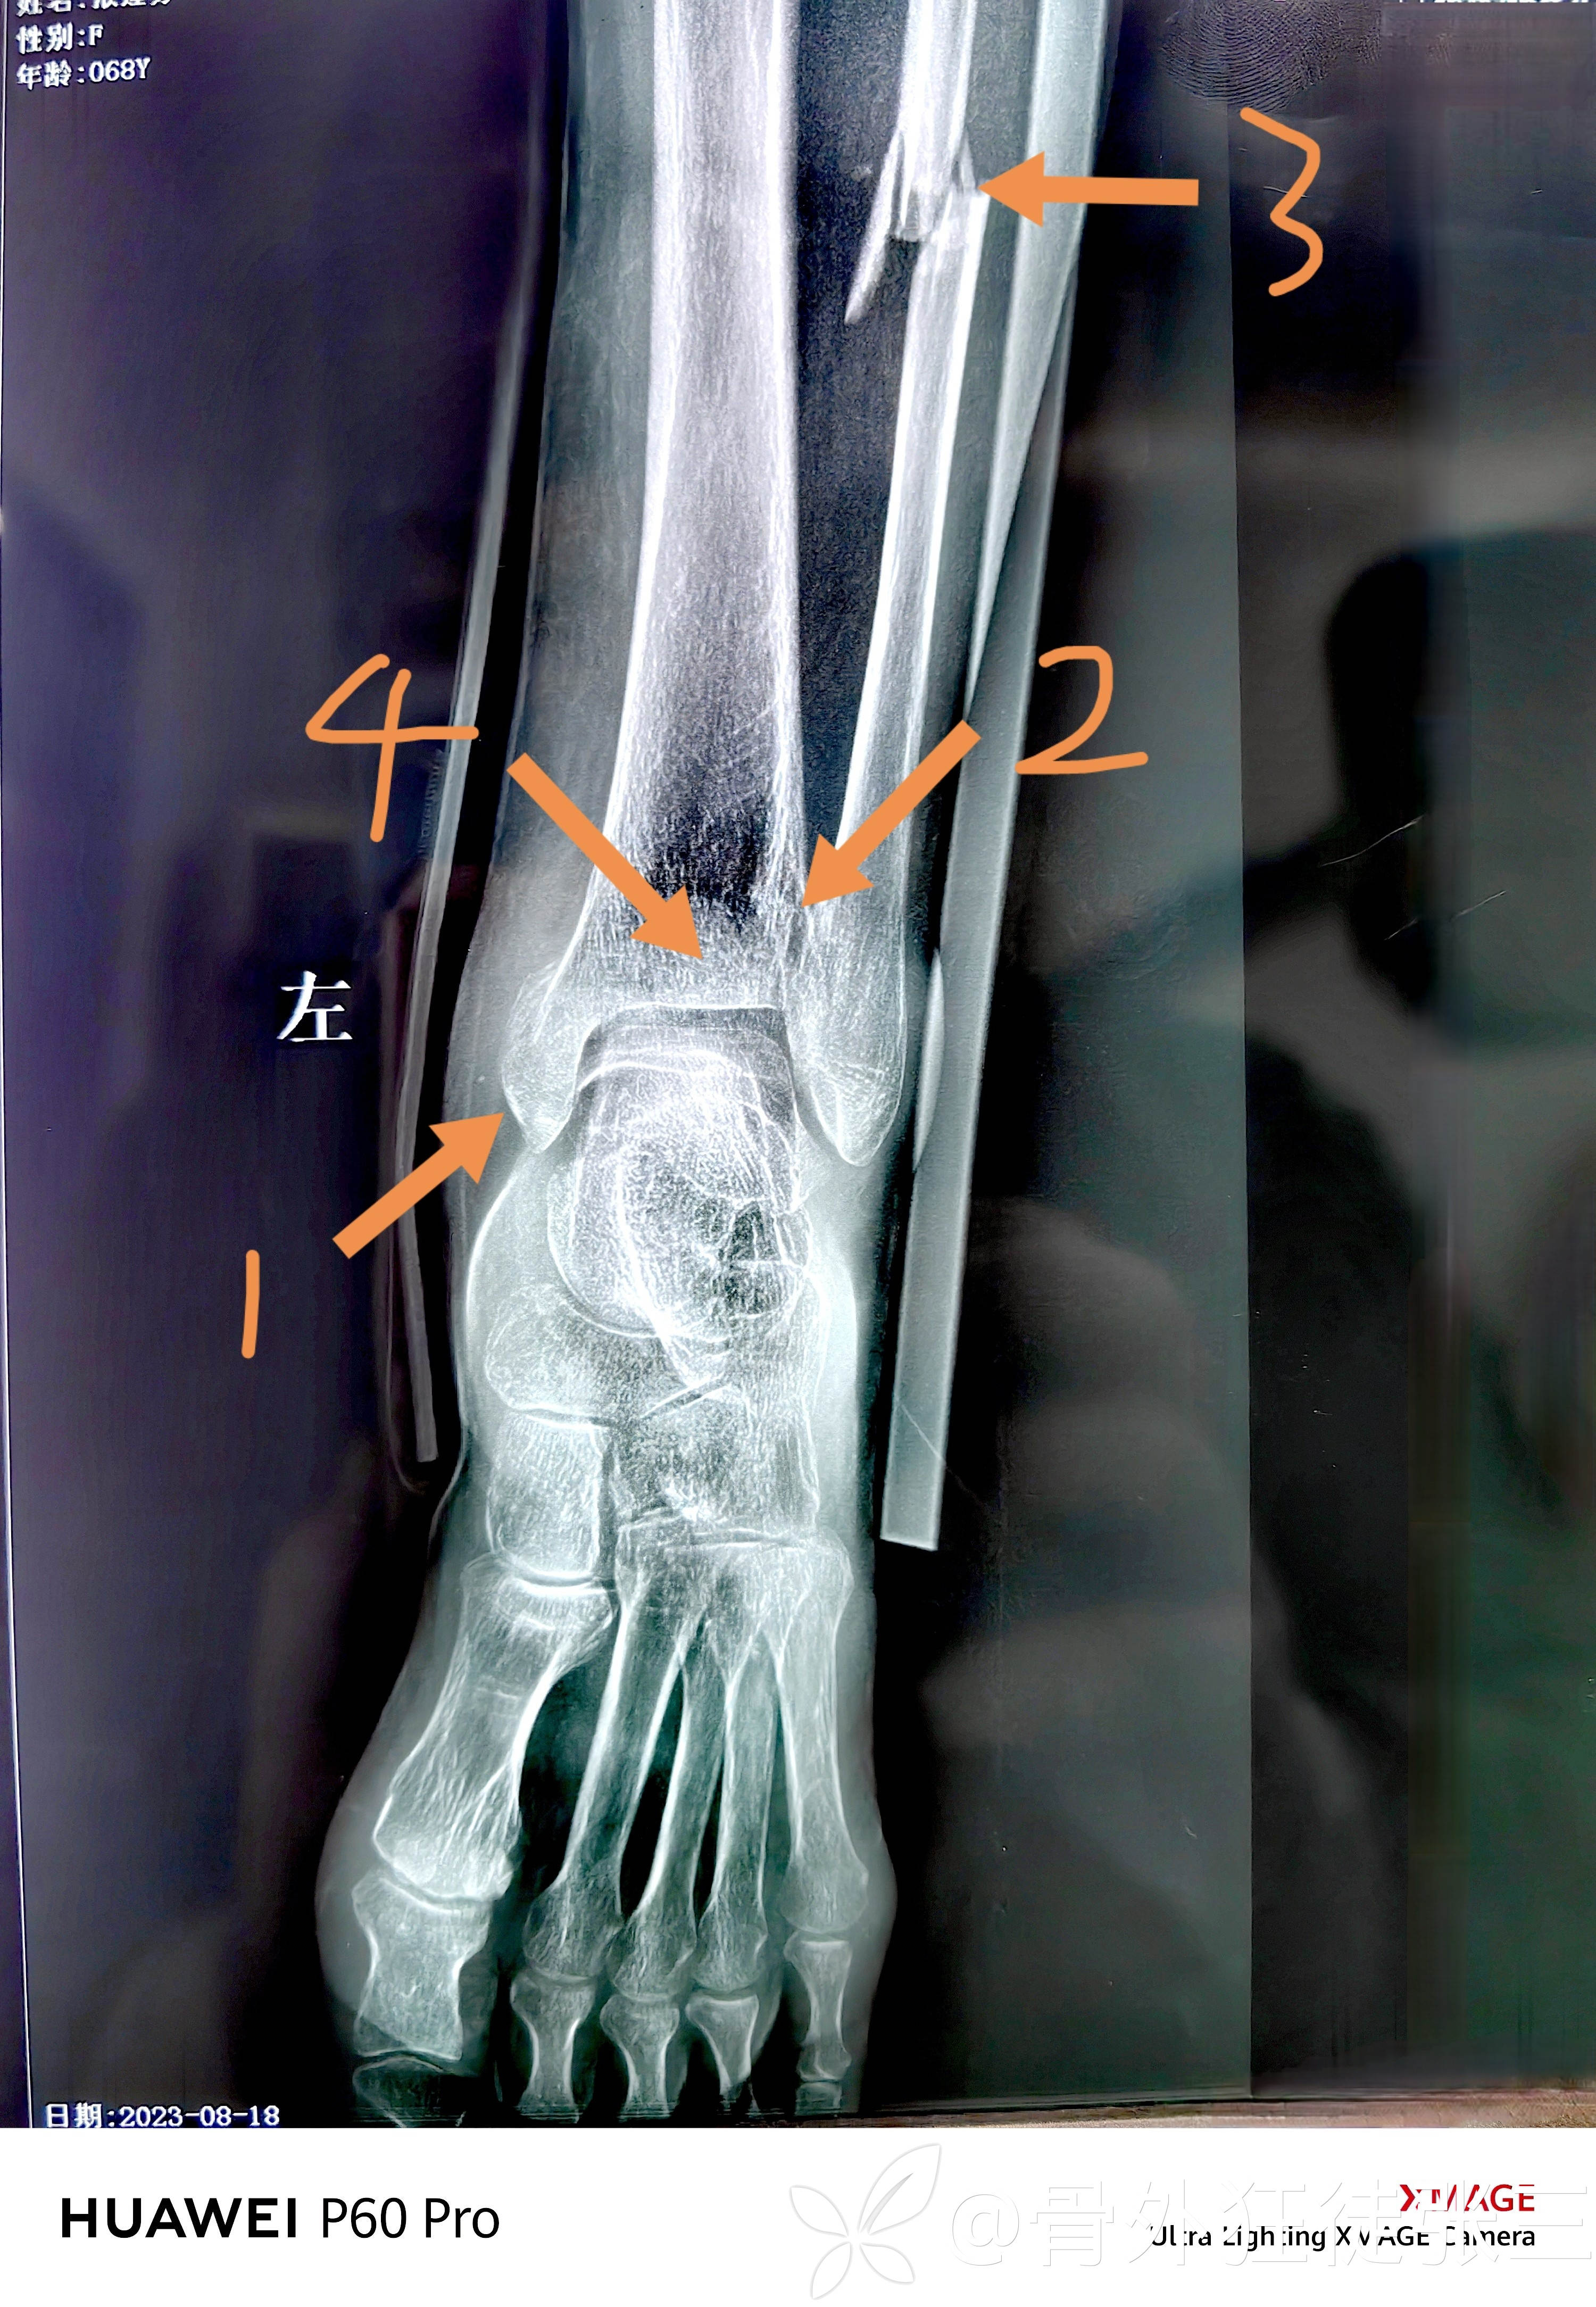

辅助检查:

高位腓骨粉碎性骨折

内踝+后踝骨折

下胫腓分离

内踝骨折,胫距关节脱位

左踝关节骨折脱位(旋前外旋4期)